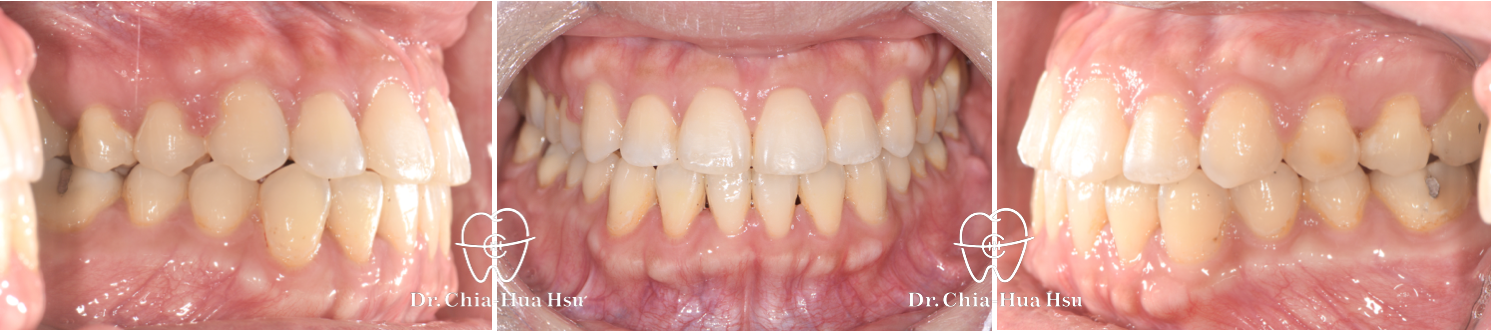

治療前

治療後